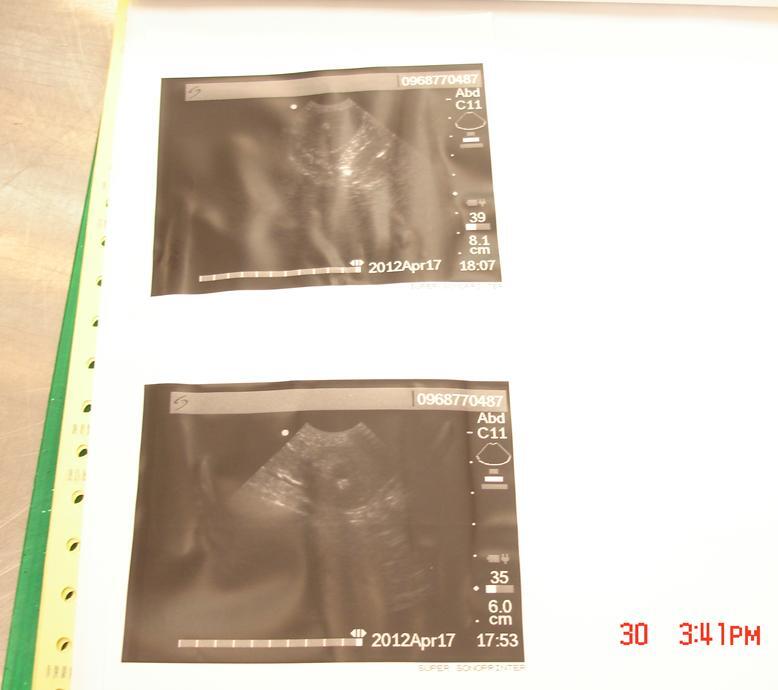

主題: 遭主人遺棄至收容所的腎結石貓開刀 part 2 申請者姓名: 劉秀珍 花色: 申請日期: 2012-04-30 16:19:50 申請者部落格: 申請者臉書網址: 所在縣市/合作醫院: 台北市/星辰動物醫院 治療費用: 27550元 需求人數: 28人 已結案 (2012-05-25 00:01:55) 報名人員: Olive Chen(已付款)、Lucida Chen(已付款)、HI HI Little(已付款)、Meng-chun Kuo(已付款)、Richard Hsu(已付款)、Shiu-Ting Chan(已付款)、Rebecca Chan(已付款)、廉雅鈺(已付款)、Garnier Huang(已付款)、Rakura Lo(已付款)、Nonie Huang(已付款)、Nonie Huang(已付款)、楊凱麟(已付款)、Tina Huang(已付款)、Estella Chen(已付款)、小王子(已付款)、波波(已付款)、Fanny Chen(已付款)、Grace Chang(已付款)、Bobby Fox(已付款)、bernice liao(已付款)、蔡小花(已付款)、baby(已付款)、Rinee(已付款)、juno(已付款)、江大雄(已付款)、珍妮郭(已付款)、Joyce Shih(已付款)、 候補人員: 動物病情說明: 3/4愛媽劉秀珍至內湖收容所領了1隻黑白貓. 送至醫院觀察. 3/5吳醫師發現貓咪排血尿和血塊. 3/10進一步檢查,拍X光後,發現貓咪左右二顆腎臟裡都有頗大結石.確診後醫師建議開刀取結石. 已於3/21開刀取出右側結石. 然後休養約4週,於4/17開刀取出左側結石. 第1次右側術後腎功能恢復迅速. 但第2次手術後恢復較慢,所以一直進行點滴輸液治療,幫助腎功能恢復. 直到4/30的血檢腎指數接近正常值邊緣. 將會再繼續點滴輸液治療幾天直到指數在正常值範圍內.

手術後有拍一張x光確認,貓咪現在2側腎臟裡都沒有結石囉! 現在就等腎功能恢復,牠就會是百分百的健康貓咪. 希望可以找到愛牠的主人. 願意給牠新的貓生. ^^